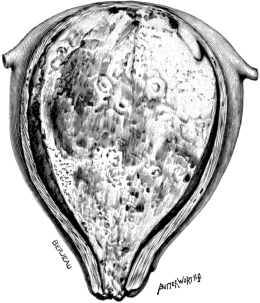

| 22. | A Uterus distorted by Fibroids | 76 |

| 23. | A Gravid Uterus in Sagittal Section | 79 |